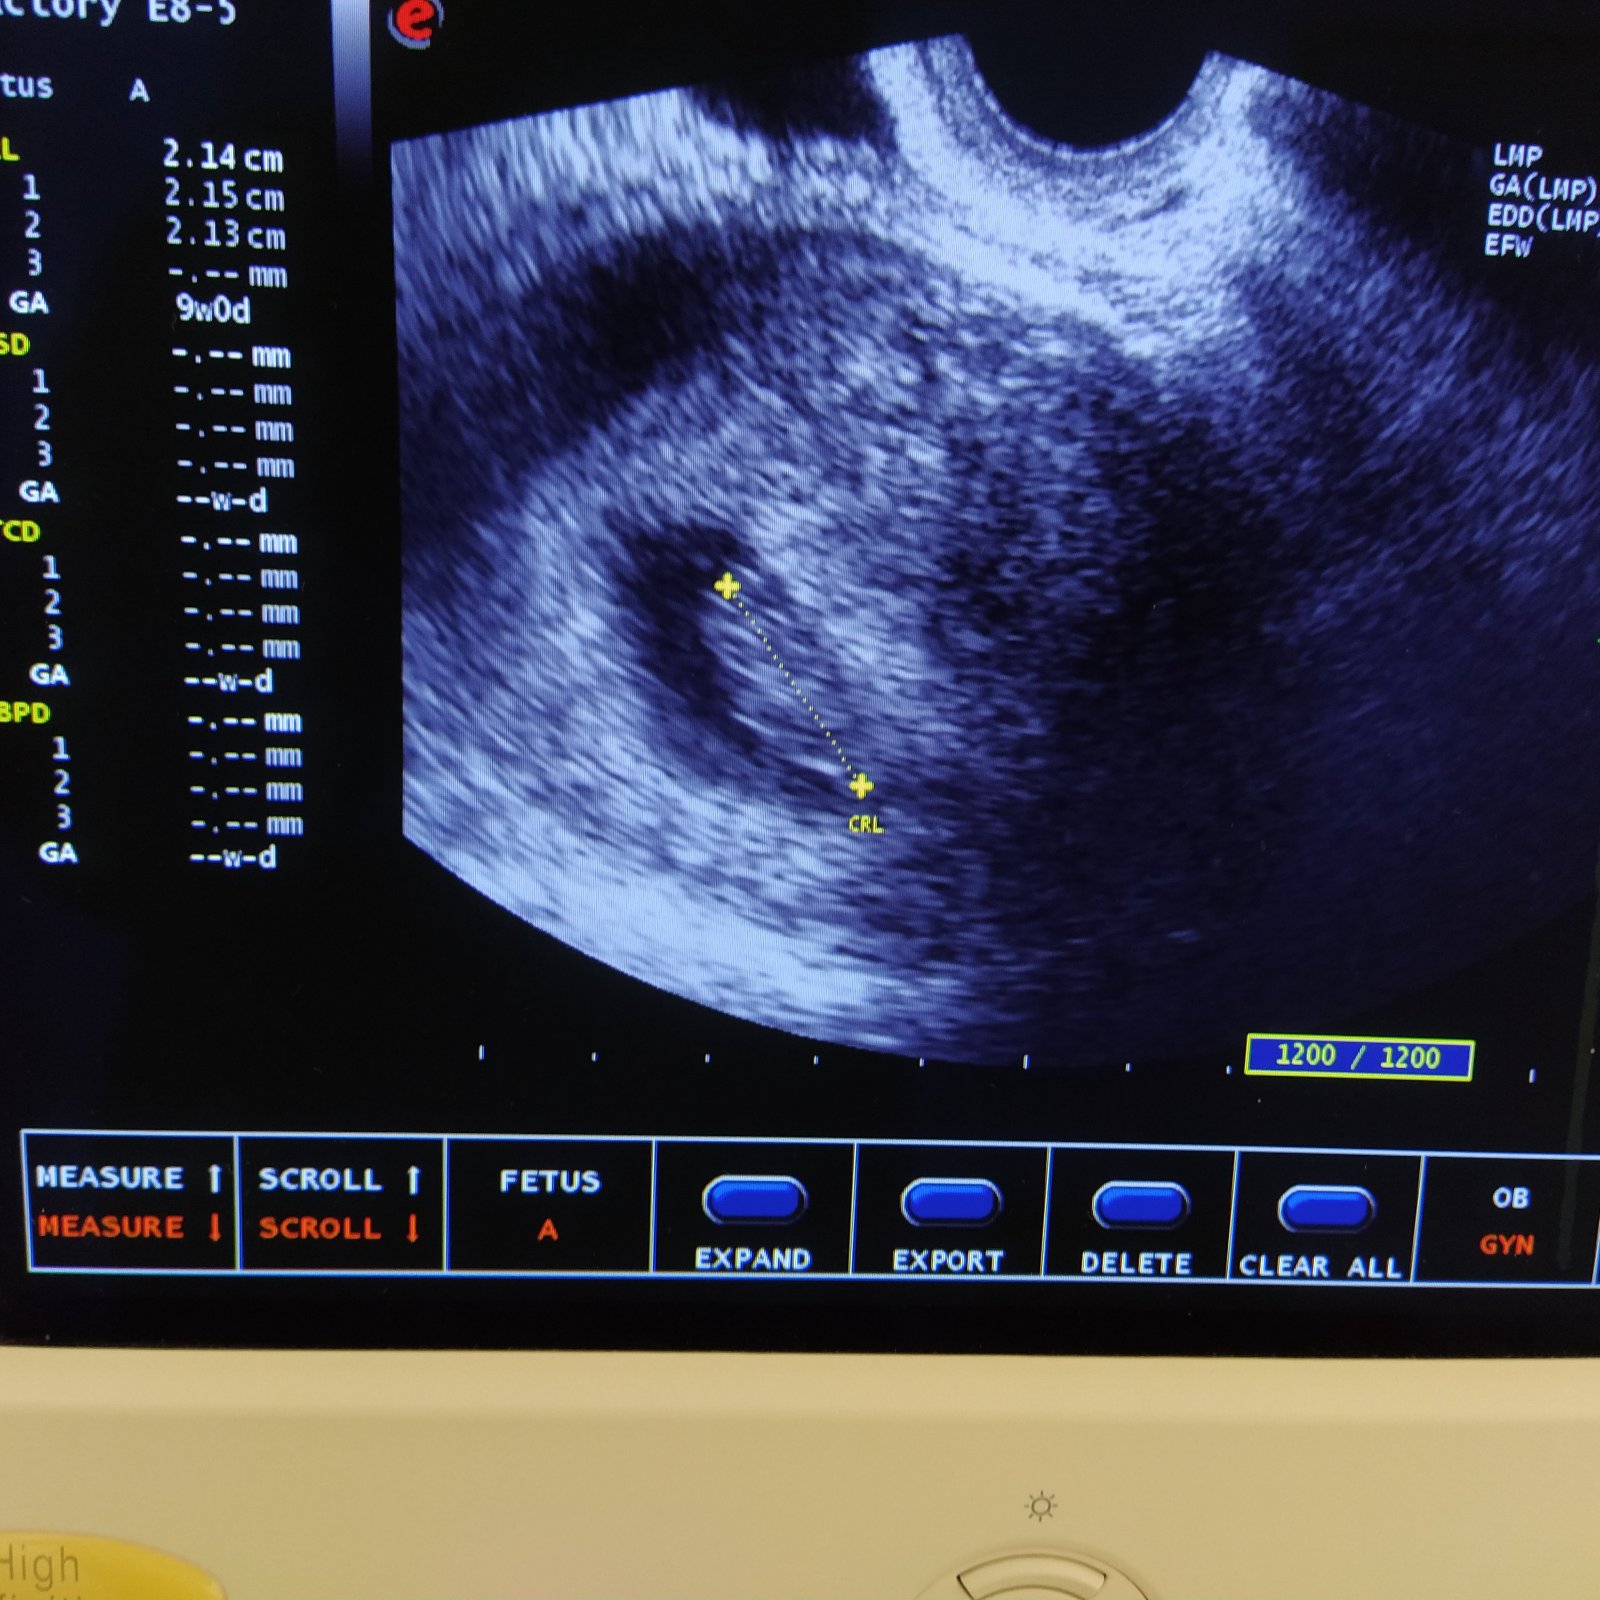

@milka1988 ahoj, hlasim sa po kontrole, vsetko v poriadku, srdiecko bije, velkost zodpoveda 9+0. Dalsiu kontrolu mam o tri tyzdne, to ma uz caka velky utz a odbery. Pridavam aj fotku, ale nic moc, schovavalo sa, ledva ho nasla🤭 maternicu mam vzadu tak asi aj preto. Hlavne ze je vsetko ok. Strasne mi po dnesnej kontrole odlahlo🤗